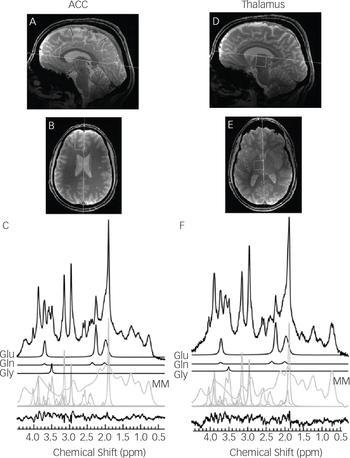

The 1H-MRS voxels were 2.0×2.0×2.0 cmReference Gilbert-Rahola and Villena-Rodriguez 3 in size and located in the left thalamus and left dorsal anterior cingulate. The left locations were chosen based on previous results by this group at lower B0.Reference Théberge, Bartha, Drost, Menon, Malla and Takhar 5 , Reference Théberge, Al-Semaan, Williamson, Menon, Neufeld and Rajakumar 9 Voxels were placed and angled using anatomical landmarks (Fig. 1) on two fast low-angle shot 2D anatomical imaging sequences in the sagittal (45 slices, repetition time (TR)=950 ms, echo time (TE)=5.23 ms, flip-angle (α)=30°, gap=1 mm, thickness=2 mm, field of view 220×220 mm, matrix size=220×220) and axial (20 slices, TR=500 ms, TE=5.23 ms, α=30°, gap=1 mm, thickness=2 mm, FOV=220×220 mm, matrix size=220×220) directions, with lipid saturation.

Fig. 1 Sagittal and transverse cross sections depicting the voxel locations in neurological orientation with example 64 average spectra in the left anterior cingulate cortex (A–C) and the left thalamus (D–F). The anteroposterior line of the corpus callosum and the midline are shown as anatomical landmarks for the sagittal and transverse cross sections, respectively. Spectral fits are shown for Glu, Gln, Gly, macromolecules (MM) and all remaining metabolites, with the residual of the fit minus the data.

The simulations of Gly and Myo demonstrated significantly improved separation of the two metabolites at 7 T compared to 1.5 T (P<0.001), 3 T (P<0.001) and 4 T (P<0.001) (Fig. 2). In vivo 1H-MRS spectra were acquired with voxels in the ACC and thalamus of all participants with the exception of one healthy control who did not wish to finish the scan of the thalamus because of dizziness. Average water linewidths were 13.2 (1.3) Hz and 16.9 (2.1) Hz for the healthy controls, 12.1 (0.9) Hz and 16.0 (1.8) Hz for the MDD group, and 12.8 (1.6) Hz and 16.9 (2.2) Hz for the schizophrenia group in the ACC and thalamus, respectively, indicating well shimmed data. There were no significant differences in the water linewidths between groups, and there were no significant differences in grey matter, white matter or cerebrospinal fluid volume per voxel between groups. One spectrum from the ACC of volunteers from each of the MDD and schizophrenia groups needed to be excluded because of poor-quality spectra, likely because of excessive movement. Example spectra from each brain region with spectral fits of Glu, Gln, Gly and the macromolecular spectrum can be seen in Fig. 1. In the thalamus, one patient from the schizophrenia group and one healthy control each presented with Gly concentrations that had CRLB of 35% and were excluded.